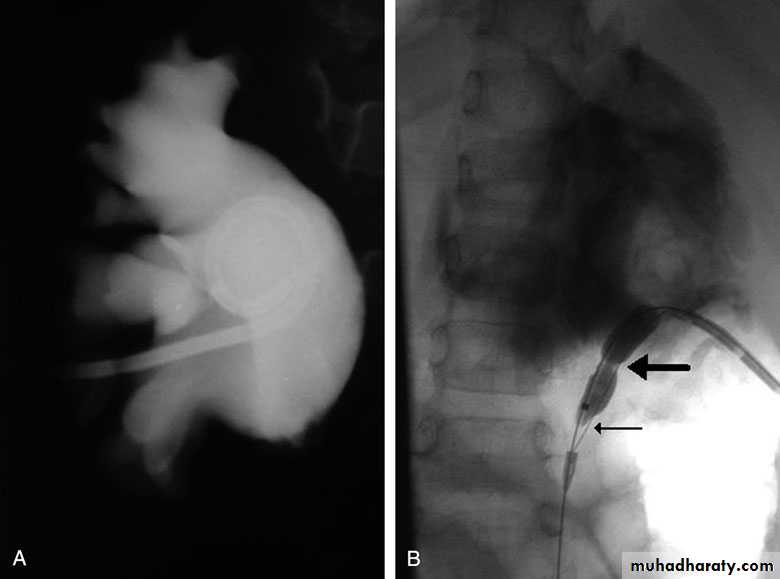

U/S: hydronephrosisIVU: diagnostic , hydronephrosis with fixed stenotic segment or complete obstruction

Pressure-Flow Studies : Whitaker testTreatment:

balloon dilatation

Antegrade endopyelotomy

Bilateral PUJO